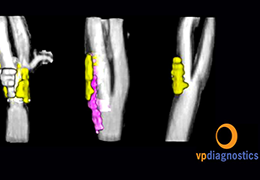

Performs 3D reconstruction and volume rendering.

Instant and interactive surface extraction and export to STL and PLY formats.